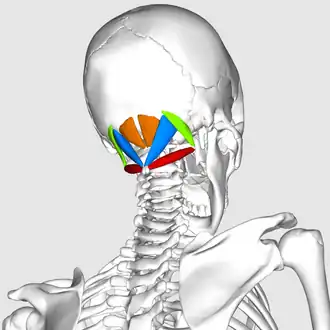

Suboccipital muscles

The suboccipital muscles are a group of muscles defined by their location to the occiput. Suboccipital muscles are located below the occipital bone. These are four paired muscles on the underside of the occipital bone; the two straight muscles (rectus) and the two oblique muscles (obliquus).

The muscles are named

- Rectus capitis posterior major goes from the spinous process of the axis (C2) to the occipital bone.

- Rectus capitis posterior minor goes from the middle of the posterior arch of the atlas to the occiput.

- Obliquus capitis superior goes from the transverse process of the atlas to the occiput.

- Obliquus capitis inferior goes from the spine of the axis vertebra to the transverse process of the atlas.

Position of suboccipital muscles. Animation.

Position of suboccipital muscles. Animation. -

Still image.

Still image.